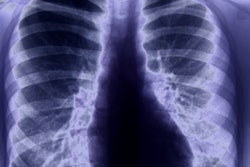

In their study, Lan's team included four patients, all of whom were medical personnel (one hospitalized, three quarantined at home) treated at Zhongnan Hospital between January 1 and February 15. All had positive RT-PCR test results and ground-glass opacification or mixed ground-glass opacification and consolidation on CT; disease severity was mild to moderate.

After hospital discharge or the end of quarantine, the patients underwent RT-PCR tests five to 13 days later. All were positive. The patients then had three more RT-PCR tests over the next four to five days, and all tested positive, although they were asymptomatic by physician examination and chest CT. None of the patients reported contact with anyone with respiratory symptoms, and none of their family members were infected.